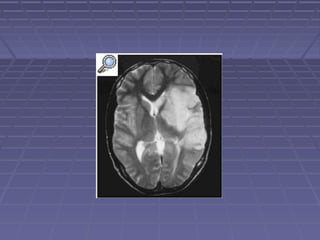

 LCR: hipercelularidad a predominio deLCR: hipercelularidad a predominio de

linfocitos, proteínas superiores a 100linfocitos, proteínas superiores a 100

mg/dl e hipoglucorraquiamg/dl e hipoglucorraquia

 TC: hidrocefalia, lesiones vasculares,TC: hidrocefalia, lesiones vasculares,

tuberculomastuberculomas